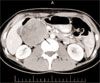

A CT scan with contrast of the abdomenreveals a well-defined massarising from the inferior aspect of thehead of the pancreas at the Oddisphincter (Figure 1). The tumor hasboth solid and cystic components, withdiffuse, inhomogeneous enhancementand no evidence of calcification. Themass is associated with mild pancreaticand biliary ductal distention. Noother abnormalities are noted withinthe abdomen or lung bases.